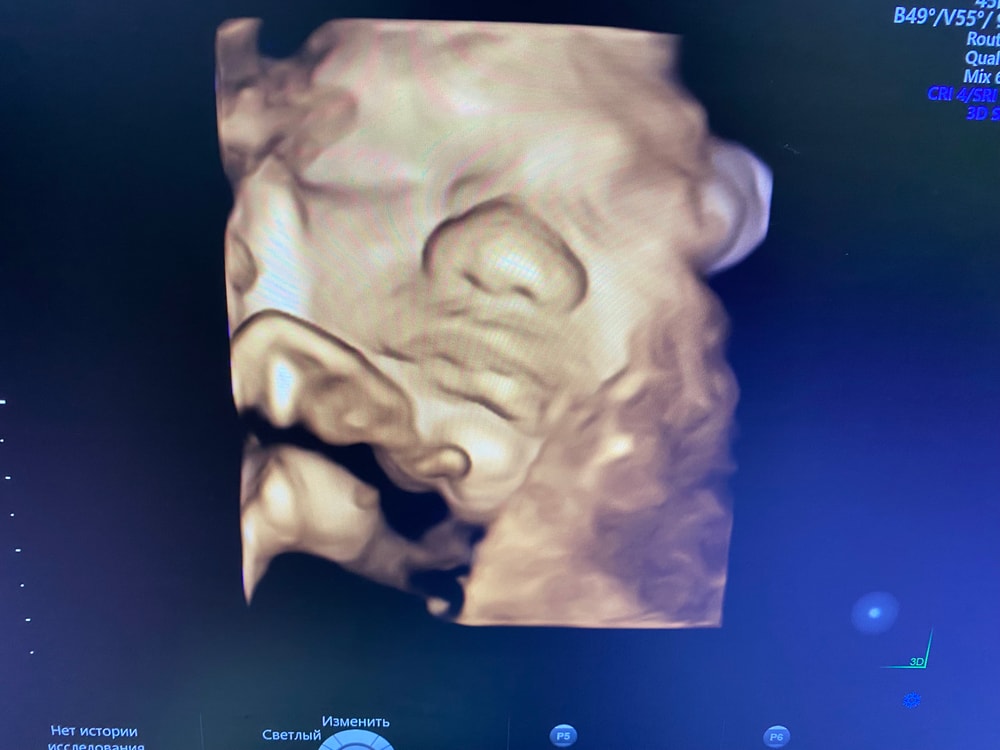

В 31 неделю еле поймали своего, он пинался, отворачивался, и постоянно закрывал руками лицо. Но если бы не получилось, я бы снова поехала бы, только в частную, чисто из-за этих фото. Это того стоит. В итоге это единственная фотка которую удалось сделать нормально. На остальных кривляется, зевает, язык вытаскивает или вообще закрывает руками 😅 Изображение

Ася , носик картошечкой🤭